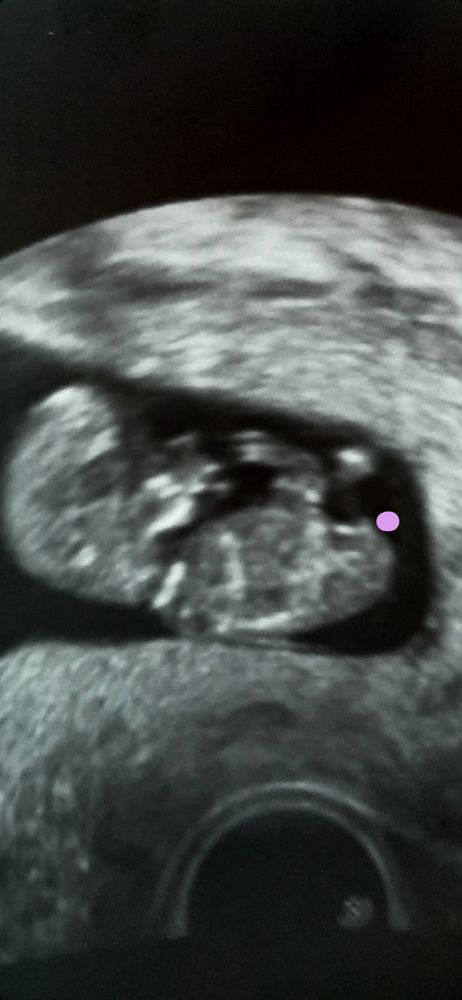

Половой бугорок?

Я думаю еще рано, но вроде бы наверх, может наконец пацан !😂🙏🏻👍🏻

Ну возможно пацан) но да рановато. Зотя бы еще 2 нед

Вполне возможно, но только непонятно, куда он смотрит. Поэтому это гадание на кофейной гуще. Срок ещё очень маленький

Вес и рост малыша в утробе матери Пол по бугорку